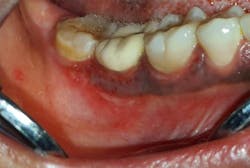

Case no. 3

The provisional diagnosis was COVID-19–related oral lesions. Topical triamcinolone acetonide (Kenacort) 0.1% paste, doxycycline and benzalkonium chloride mouthrinses, and topical benzocaine 5% gel were prescribed three times per day.

- Multiple palatal and oropharyngeal petechial lesions

- Palatal and oropharyngeal erosions and ulcerative lesions

- Excessive salivation

- Severe pain over the lesion area

- Partial paresthesia surrounding the lesions

- Irregular areas of blanching involving the palate

- Burning sensation of palate and oropharynx, and dysphagia

- Palatal and oropharyngeal tenderness and soreness

- Necrotic pseudomembranes covering the erosive/ulcerative lesions